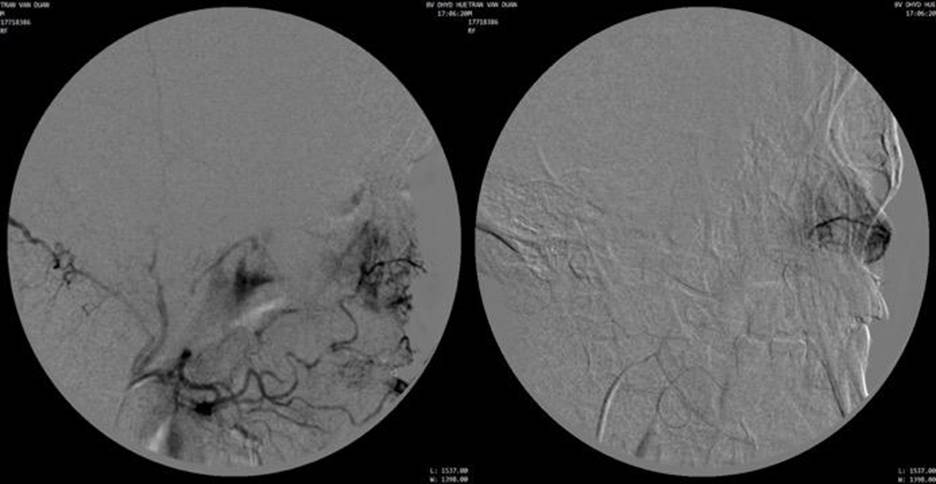

Chọn lọc động mạch hàm, tiếp cận động mạch huyệt răng sau trên. Chụp chọn lọc thấy khối tăng sinh mạch với hình ảnh tumor network. Bơm tắc ngoại vi bằng hạt PVA 250-355μm. Nút tắc gốc bằng 01 detachable coil Interlock 5x150mm.

Chụp kiểm tra thấy tắc hoàn toàn mạch nuôi u, không thấy phần u ngấm thuốc.

Hình 5: Chụp mạch chọn lọc nhánh nuôi u từ động mạch huyệt răng sau trên phải (từ động mạch hàm)

Hình 6: Chụp kiểm tra sau nút mạch không còn thấy u ngấm thuốc